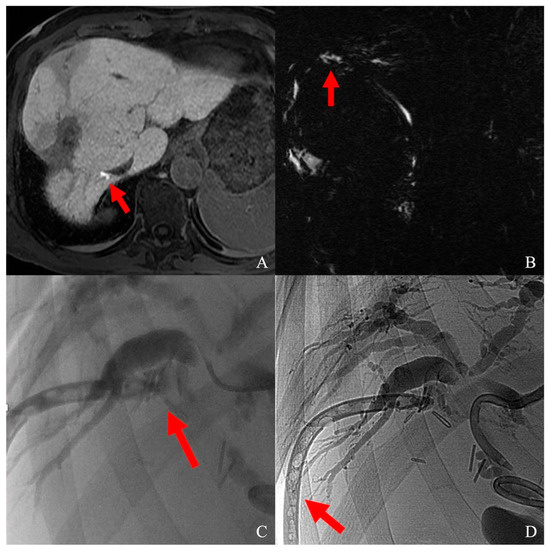

2.2. Laparoscopic and Laparotomic Ablation